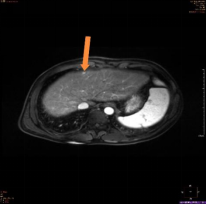

(图1)

上图为一名53岁男性,乙肝、肝硬化随访复查,AFP及超声检查均为阴性;图1为腹部CT平扫显示,肝左叶体积增大,肝实质内未见明确异常密度结节及肿块;图2、图3分别为磁共振平扫T2WI、弥散成像显示,肝左内叶上段见一直径为0.8cm的稍高信号结节(箭头所示);图4为T1WI增强动脉期显示,该结节动脉期高强化(箭头所示);该病人为肝癌高危人群,磁共振扫描高度怀疑此异常信号结节为早期小肝癌,患者遂到上级医院手术,术后病理证实为肝细胞肝癌。